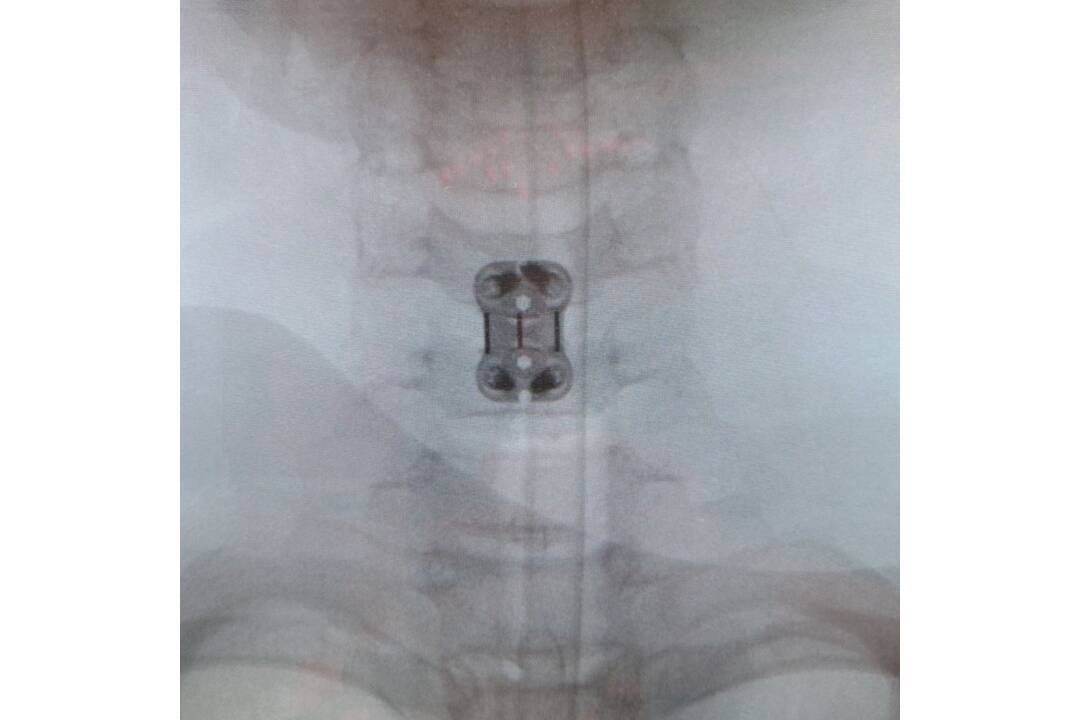

FOTO: Neurochirurgovia NÚDCH operovali vážne úrazy chrbtice, deti mohli skončiť na vozíku

FOTO: Neurochirurgovia NÚDCH operovali vážne úrazy chrbtice, deti mohli skončiť na vozíku, foto 2

Zdroj: Facebook/Národný ústav detských chorôb